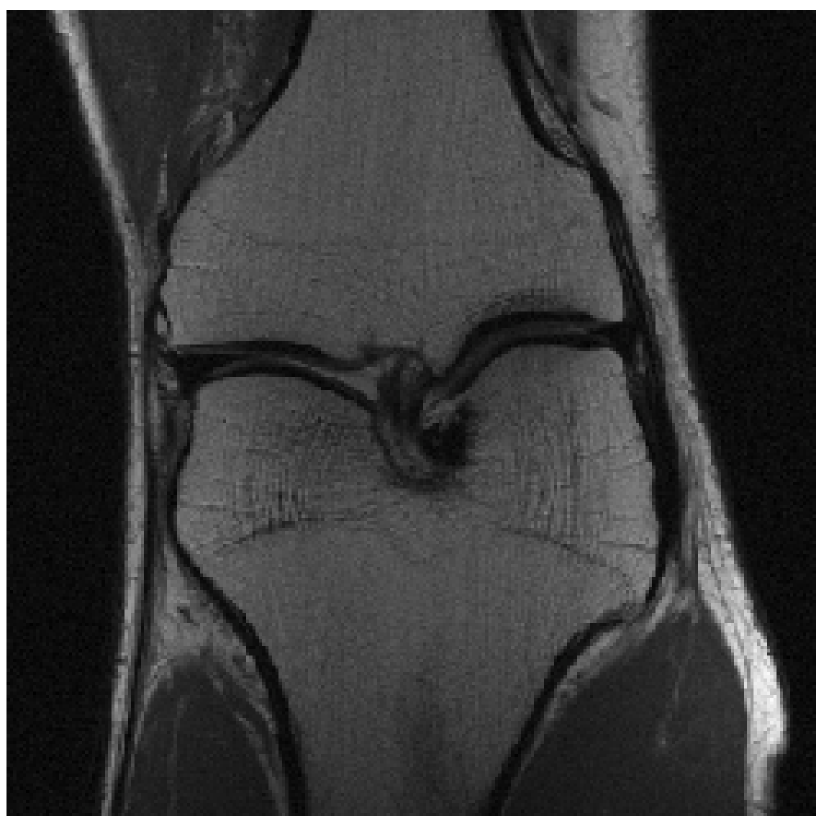

We evaluated our models on three data sets: the validation set as in Zbontar et al. (2018), and the test and challenge sets through the fastMRI website. A summary of these evaluations can be found in table 1111Results on the challenge data set will be added once publicly available.. To assess image quality more closely, we show some exemplary reconstructions from each model in figure 1.

Ground Truth

Reconstruction

Reconstruction